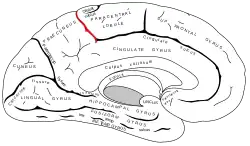

Medial surface of left cerebral hemisphere. (Marginal sulcus shown in red.) | |

In neuroanatomy, the marginal sulcus (margin of the cingulate sulcus) is a sulcus (crevice) that may be considered the termination of the cingulate sulcus. It separates the paracentral lobule anteriorly and the precuneus posteriorly.

Position of marginal sulcus (shown in red).